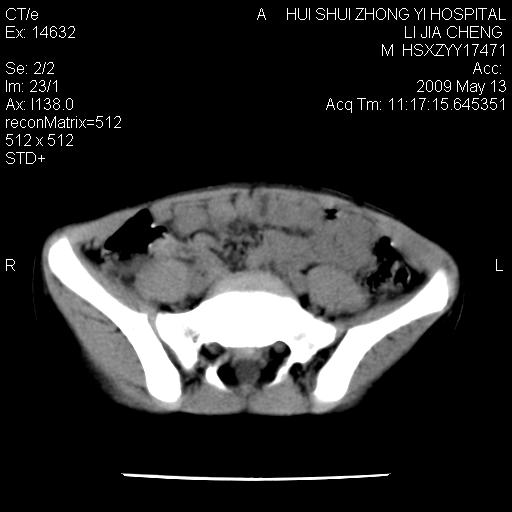

标题: PED1887:男性,6岁。反复脐周疼痛2年余。请各位老师看下腹 [打印本页]

标题: PED1887:男性,6岁。反复脐周疼痛2年余。请各位老师看下腹

该患者可自行好转,大小便未见异常,化验:便未见虫卵,血常规:wbc:8000;淋巴3600,中性45%

肠道准备不足,im15---------------------18左侧腹腔病变?